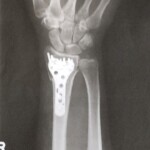

手首に入ったプレート